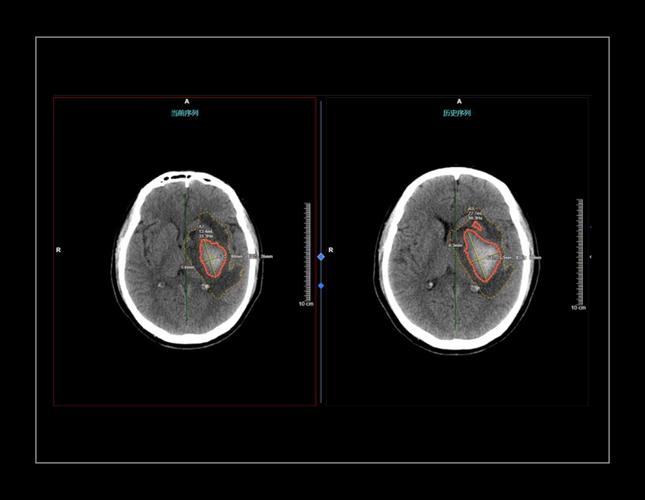

- 急性脑卒中分诊:

- 应用: 在急性卒中救治中,时间就是大脑,AI可以在数分钟内完成头颈部CTA的自动分析,快速识别大血管闭塞,并量化缺血核心和缺血半暗带体积,为急诊溶栓或取栓决策提供关键支持,大大缩短了救治时间。